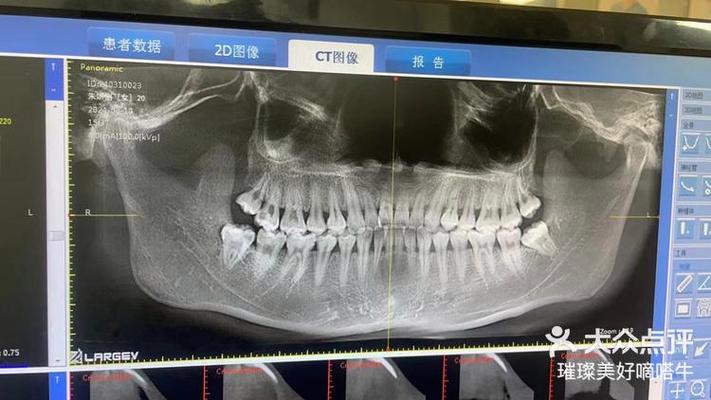

| 全景片(曲面断层片) | 观察全口牙齿排列、牙根形态、牙槽骨高度、第三磨牙位置、颌骨病变及发育情况 | 优点:辐射低(约0.007mSv)、费用低、可显示全口牙列;缺点:二维重叠、细微结构模糊 | 常规正畸初筛,了解牙齿数目、萌出顺序、牙根有无吸收、牙槽骨整体状况 |

| CBCT(锥形束CT) | 三维重建颌骨、牙齿、神经血管位置,清晰显示埋伏牙方向、牙根与骨皮质关系、上颌窦及下颌管位置 | 优点:三维立体、分辨率高、可任意角度旋转;缺点:辐射高于全景片(约0.1-0.3mSv)、费用高 | 复杂病例(如埋伏牙牵引、正颌手术术前评估、骨量不足需植骨者、颞下颌关节紊乱检查) |

正畸医生需结合全景片、头颅侧位片、CBCT等多源影像,结合临床检查(模型、口内照、面部分析)进行综合解读,对于“牙列拥挤”患者,全景片需观察牙根有无弯曲、吸收,牙槽骨高度是否支持牙齿移动;头颅侧位片需分析拥挤是否由颌骨发育不足(如上颌骨狭窄)导致,以决定是否需要扩弓或拔牙矫治,CBCT则可明确牙槽骨厚度,判断隐形矫治附件粘贴的可行性,或正颌手术中骨块移动的安全范围。

A:全景片虽能显示全口牙列,但属于二维重叠影像,对埋伏牙、牙根与骨皮质关系、颌骨内重要解剖结构(如下牙管、上颌窦底)的显示存在局限,CBCT可三维重建颌骨和牙齿,清晰呈现埋伏牙的位置、方向及与邻牙的关系,帮助医生设计精准的牵引方案;对于正颌手术患者,CBCT能模拟骨块移动路径,避免损伤神经血管;对牙根吸收、骨皮质穿孔等细微病变的检出率也显著高于全景片,复杂病例需通过CBCT获取更全面的信息,确保治疗安全与效果。